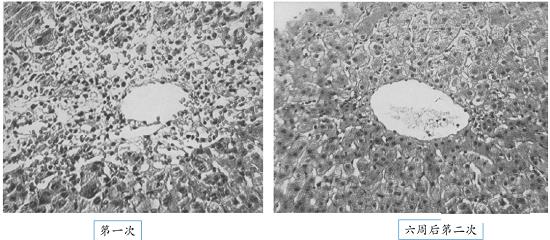

乙硫异烟胺肝损的临床及病理特点